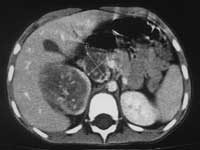

Рис. 4. Нефробластома правого надпочечника у у б-го С., 1,5 лет.

(а) Нативное КТ-исследование.

Рис. 4. Нейробластома правого надпочечника у б-го С., 1,5 лет.

(б) КТА. НПВ компремирована, располагается в толще опухоли. Сброс венозной крови в полунепарную вену. Деформация и отклонение правой почечной артерии.